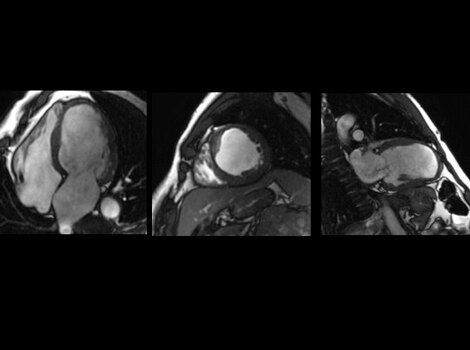

SIGNA Works CV Imaging & Analysis Tools

A free breathing, cardiac MR to assess cardiac morphology,function, flow, tissue viability and coronary anatomy without ionizing radiation.  Read More

A non invasive cardiac MR to assess cardiac morphology, function, flow,tissue viability and coronary anatomy without ionizing radiation. Read More

A non invasive cardiac MR to assess cardiac morphology, function, flow, tissue viability and coronary anatomy without ionizing radiation.

SIGNA™ Works CV Imaging & Analysis Tools

A non invasive cardiac MR to assess card ac morphology, function, flow,tissue viability and coronary anatomy without ionizing radiation. Read More